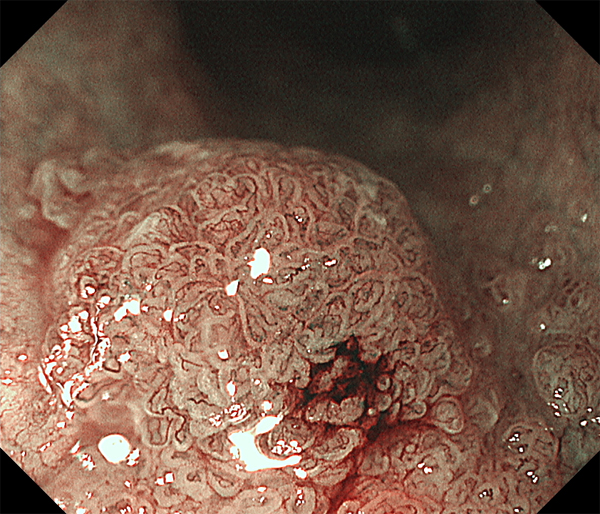

2026年1月24日開催の第19回研究会でご提示した検討症例です。 (画像をクリックすると拡大します)

2025年7月19日開催の第18回研究会でご提示した検討症例です。 (画像をクリックすると拡大します)

2025年1月11日開催の第17回研究会でご提示した検討症例です。 (画像をクリックすると拡大します)

2024年6月29日開催の第16回研究会でご提示した検討症例です。 (画像をクリックすると拡大します)

2024年1月6日開催の第15回研究会でご提示した検討症例です。 (画像をクリックすると拡大します)

2023年7月1日開催の第14回研究会でご提示した検討症例です。 (画像をクリックすると拡大します)

2023年1月21日開催の第13回研究会でご提示した検討症例です。 (画像をクリックすると拡大します)

2022年7月2日開催の第12回研究会でご提示した検討症例です。 (画像をクリックすると拡大します)

2022年1月22日開催の第11回研究会でご提示した検討症例です。 (画像をクリックすると拡大します)

2021年6月26日開催の第10回研究会でご提示した検討症例です。 (画像をクリックすると拡大します)

2021年1月23日開催の第9回研究会でご提示した検討症例です。 (画像をクリックすると拡大します)

2020年1月25日開催の第8回研究会でご提示した検討症例です。 (画像をクリックすると拡大します)

2019年1月12日開催の第6回研究会でご提示した検討症例です。 (画像をクリックすると拡大します)

2018年6月30日開催の第5回研究会でご提示した検討症例です。 (画像をクリックすると拡大します)

2017年7月15日開催の第3回研究会でご提示した検討症例です。 (画像をクリックすると拡大します)

2017年1月7日開催の第2回研究会でご提示した検討症例です。 (画像をクリックすると拡大します)

2016年6月4日開催の第1回研究会でご提示した検討症例です。 (画像をクリックすると拡大します)